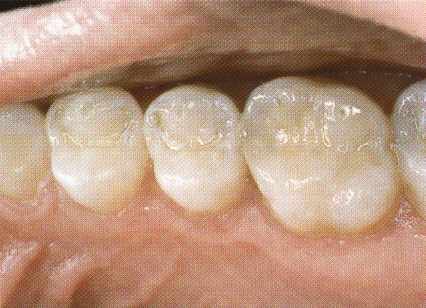

Een amalgaamvulling versterkt de kies niet. Daardoor is aan de tongzijde de knobbel van de kies afgebroken naast de vulling.

De hele vulling is verwijderd en met composiet is de kies hersteld.